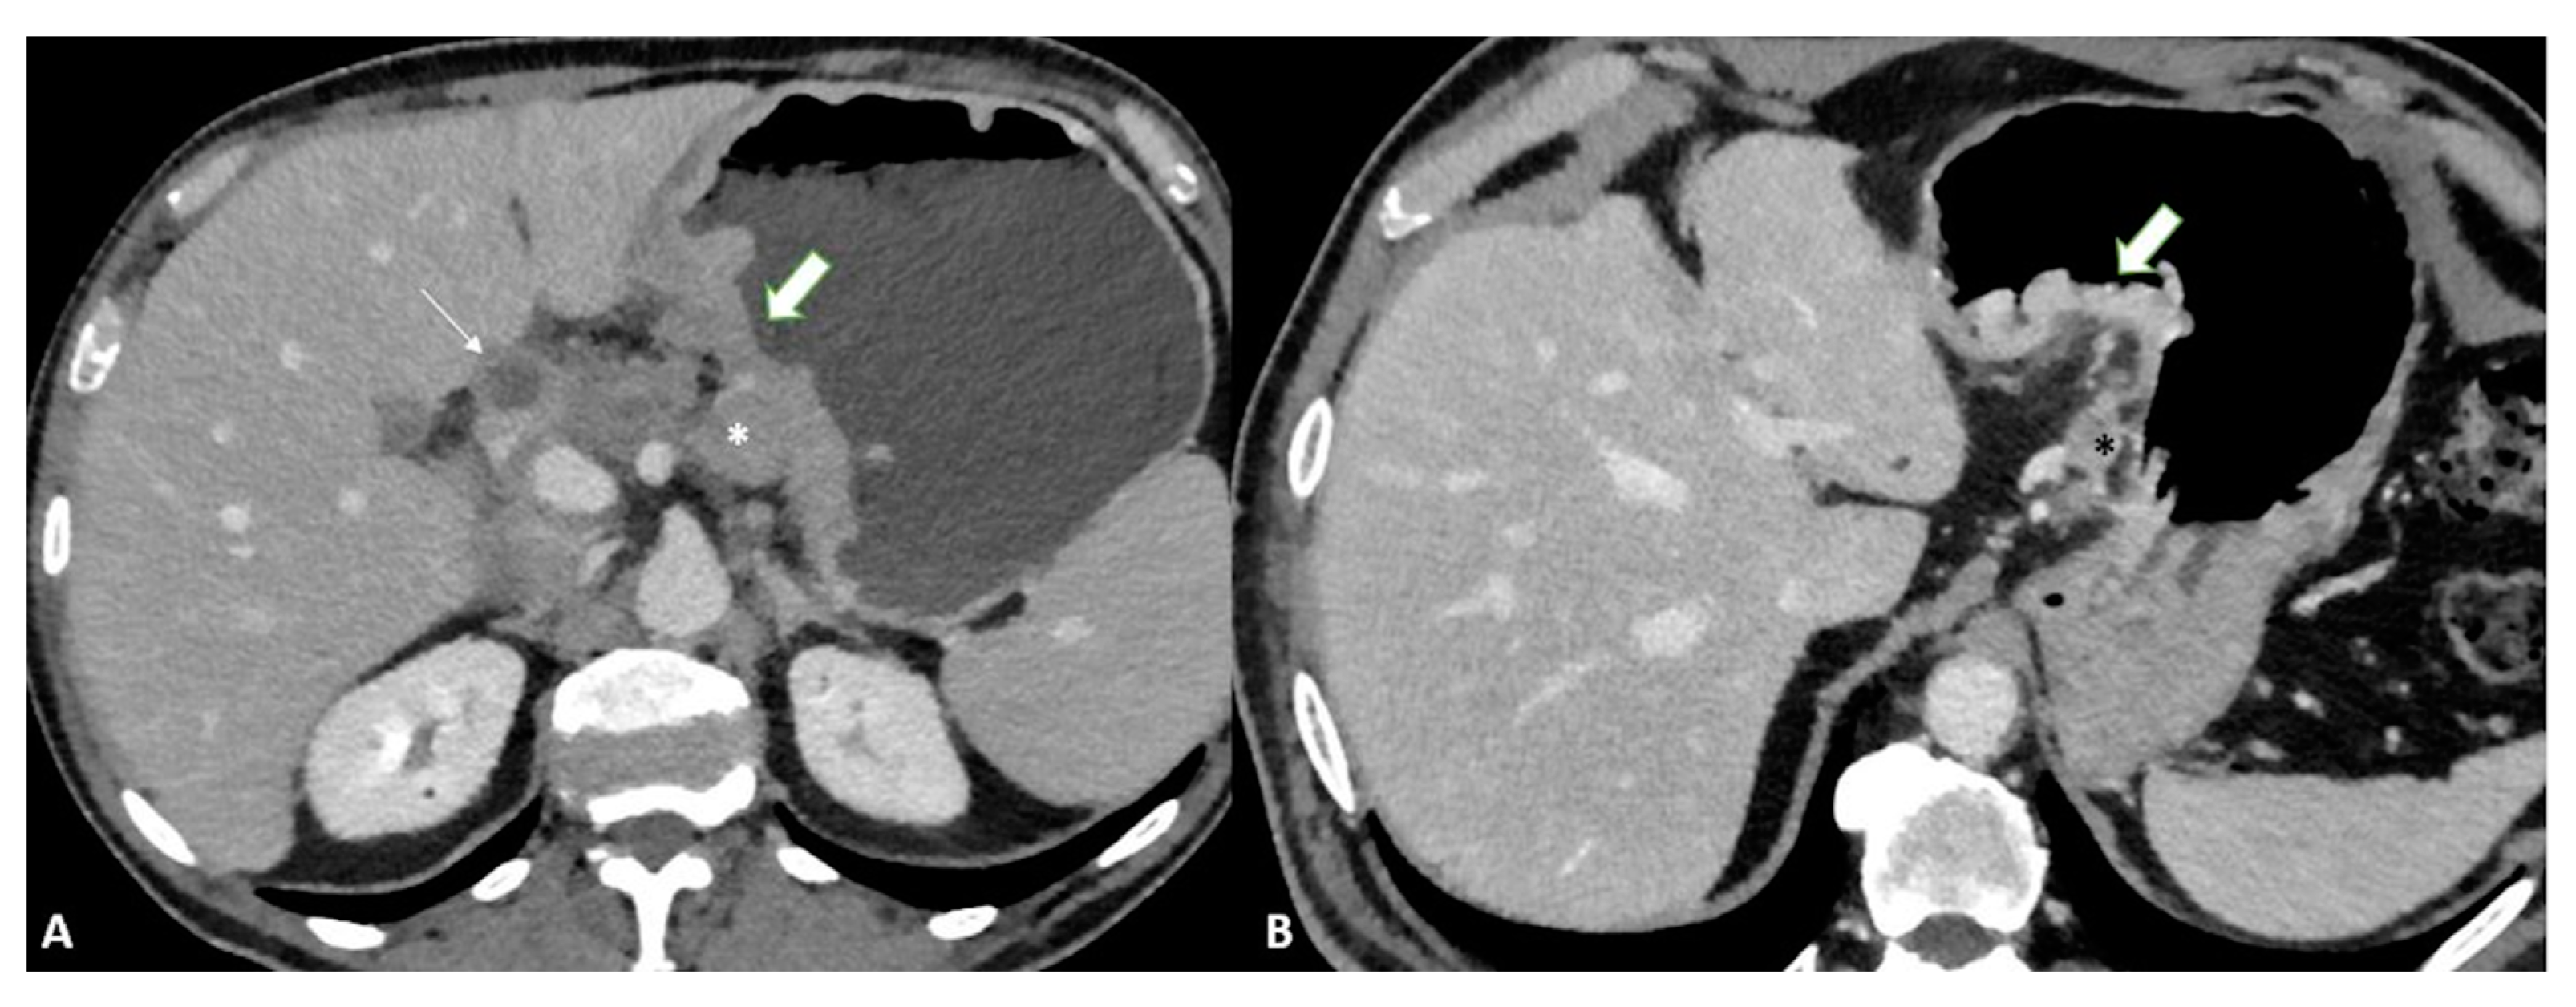

T4b shows extension into an adjacent structure and shows the loss of the fat plane between the gastric mass and adjacent organs (Figure 5).

Figure 5.

T4b gastric cancer in a 74-year-old female patient. (A,B). Axial 2D images in the portal venous phase and (C) Coronal multiplanar reconstruction showing (thick arrows) a bulky tumor of the middle-low body of the stomach and of the gastric antrum with necrotic-colliquative components inside, ulcerative alterations and some solid deposits (black asterisks) in the perivisceral fat tissue. The tumor fistulizes and infiltrates the transverse colon (thin arrows).

The added value of MPR combined with VG can increase the overall accuracy (from 73 to 89%) thanks to its ability to better assess invasion (Figure 6) [30].

Figure 6.

T4a gastric cancer in a 53-year-old female patient. (A) Axial 2D image in the portal venous phase with distension of the gastric lumen with air shows a bulky circumferential tumor (white arrows) of the low body of the stomach and of the gastric antrum with ulcerations; (B) Virtual gastroscopy delineates a lesion protruding in the lumen of the stomach; (C) Computed tomography gastrography shows a mucosal irregularity (white arrows) with a reduction of the lumen of the stomach.

To confirm this hypothesis, other studies have reported that VG can enhance the recognition of GC, especially EGC [31]. In support of these data, it has been demonstrated [32] that VG can increase the overall performance compared to axial images alone in detecting EGC with sensitivity and specificity levels of 91.9% and 74% and 62.9% and 82.9%, respectively (Figure 7).

Figure 7.

T3 gastric cancer in a 68-year-old female patient. Contrast enhanced CT with gastric distension using air. (A) Axial 2D image and (B) Coronal 2D image in the portal venous phase with distension of the gastric lumen with air showing a semicircumferential tumor (white arrows) of the low body of the stomach with ulcerations.